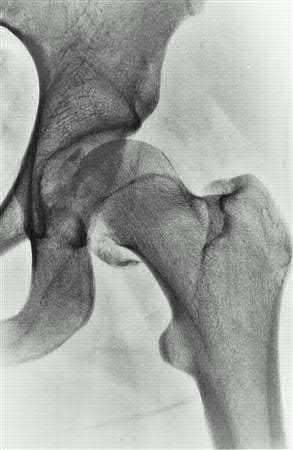

A 13-year-old obese boy presents with non-traumatic knee pain and is noted to have an obligate external rotation of his hip when it is passively flexed. Radiographs confirm the diagnosis. He is unable to bear weight on the affected extremity. What is the primary complication associated with this presentation compared to a patient who is able to bear weight?

Options:

- Chondrolysis

- Avascular necrosis (AVN) of the femoral head

- Femoroacetabular impingement (FAI)

- Slipped capital femoral epiphysis on the contralateral side

- Leg length discrepancy

Correct Answer: Avascular necrosis (AVN) of the femoral head

Explanation:

The patient has an unstable slipped capital femoral epiphysis (SCFE), defined by Loder criteria as the inability to bear weight even with crutches. Unstable SCFE has a significantly higher rate of avascular necrosis (up to nearly 50% in some series) compared to stable SCFE (which has an AVN rate near 0%). Both stable and unstable SCFEs can lead to impingement or contralateral slips, but AVN is the critical distinguishing risk factor of an unstable slip.